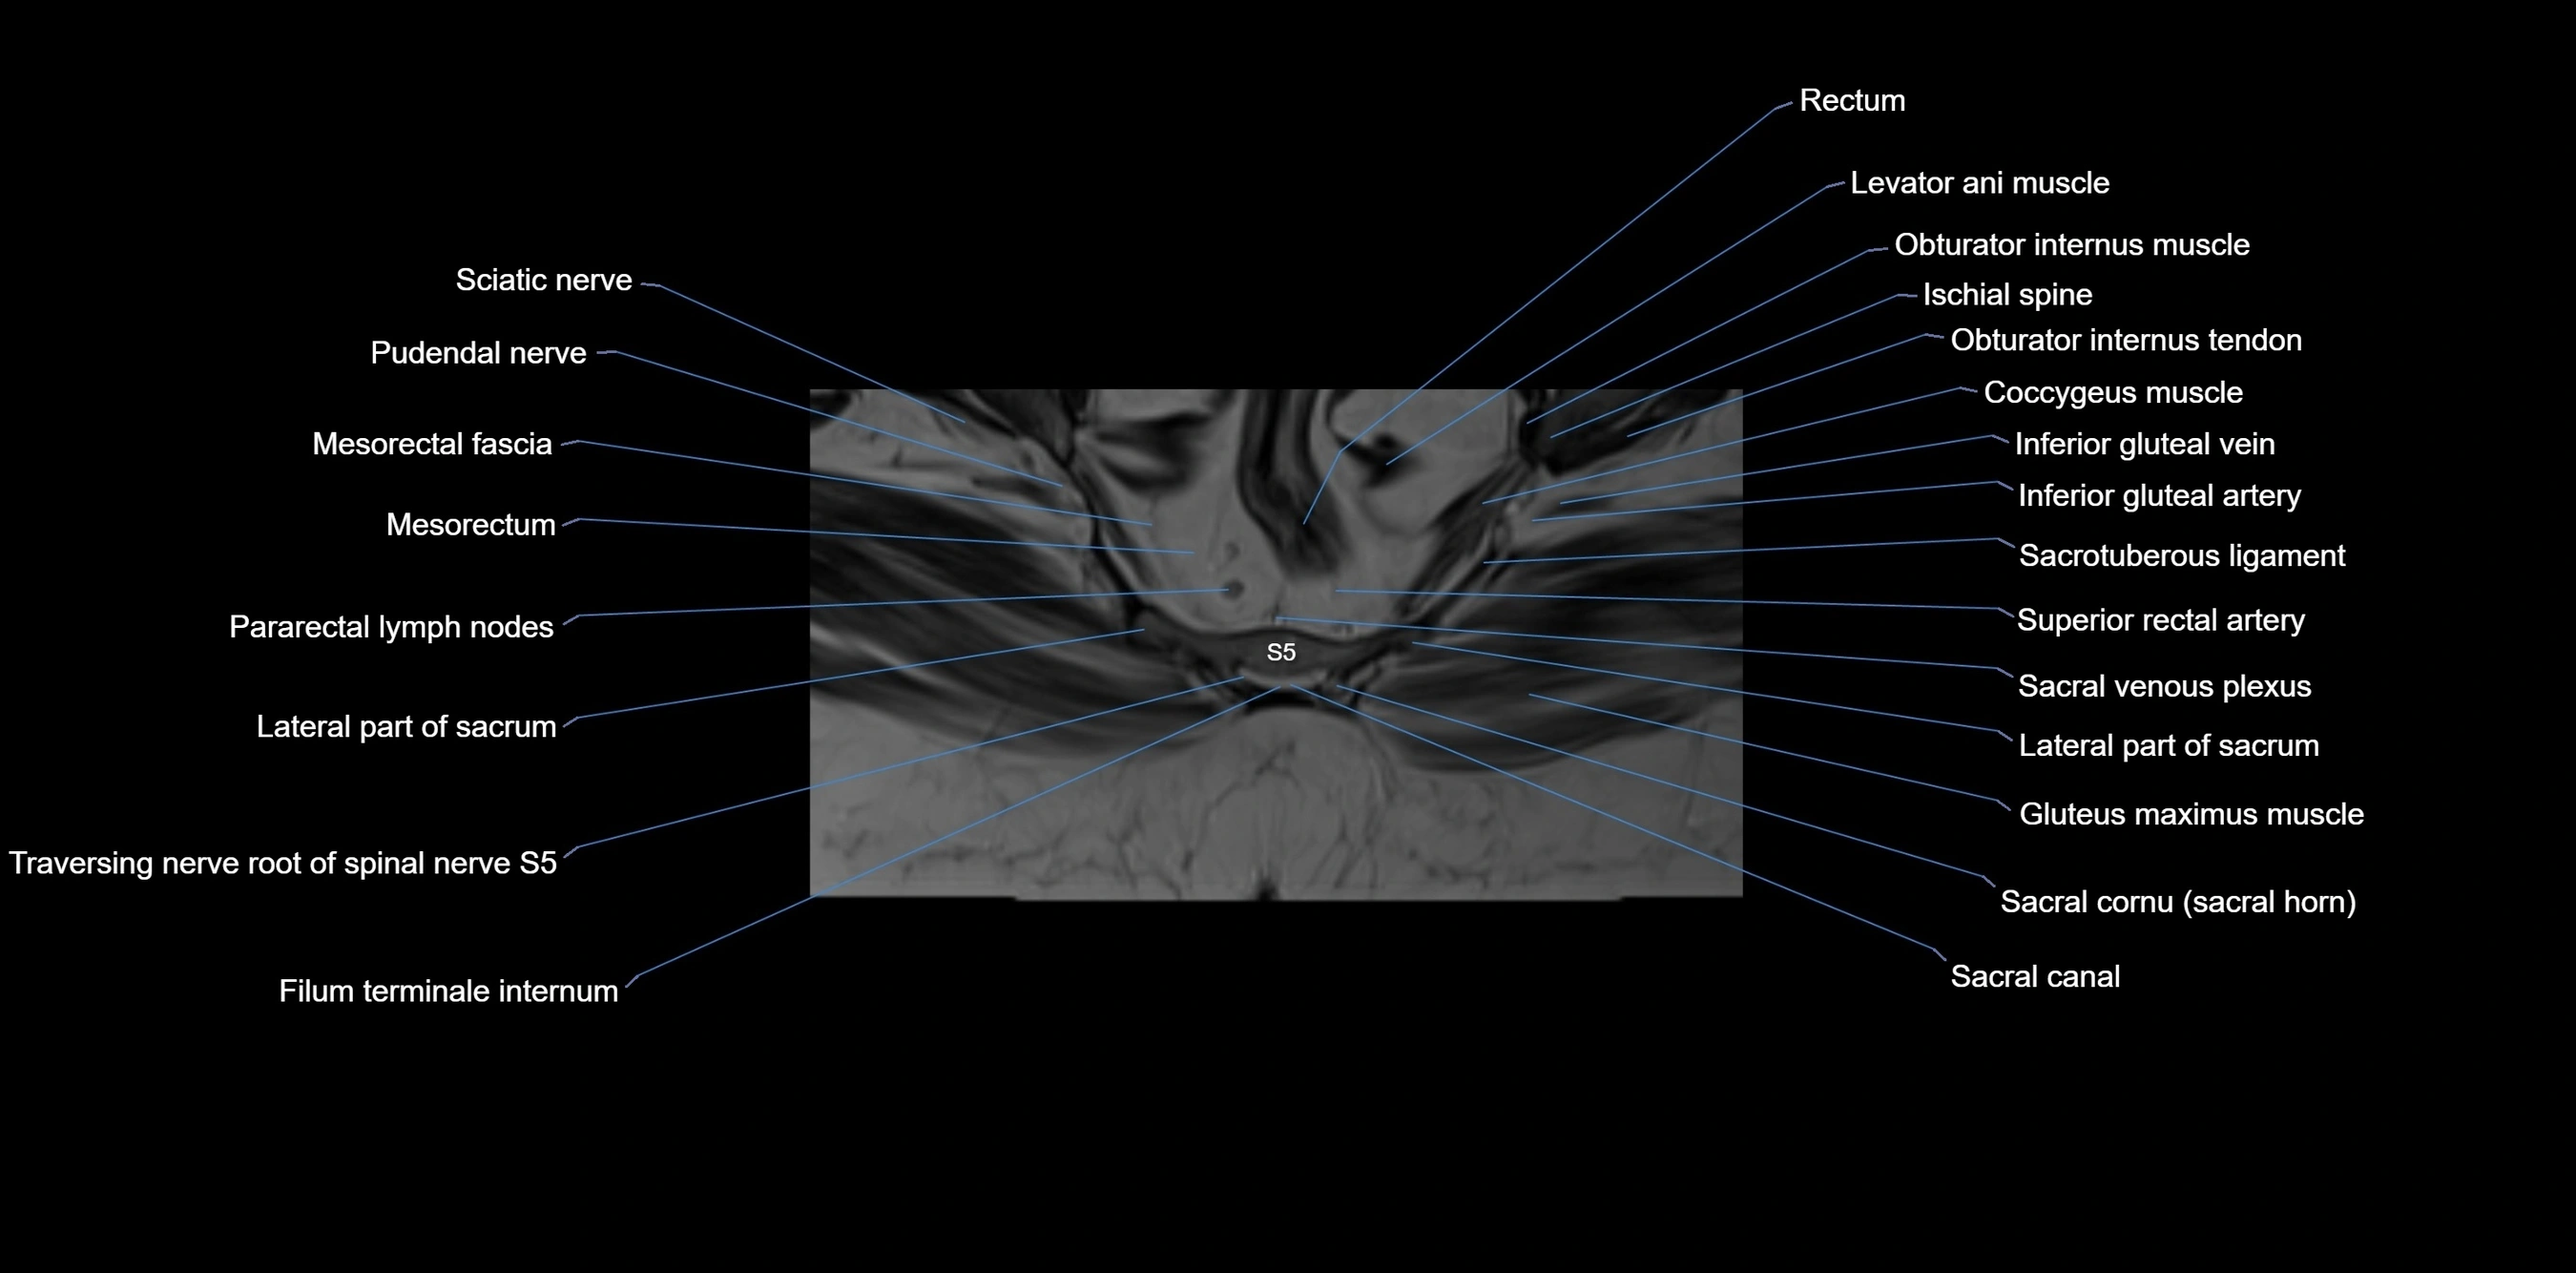

MRI image

image

MRI Appearance

T1-weighted images:

• Cortical bone appears very low signal (dark); marrow shows intermediate signal

• Iliac fossa fat is bright against low-signal cortex

T2-weighted images:

• Cortical bone remains dark

• Marrow signal varies depending on fat content; edema or tumor shows hyperintensity

STIR:

• Suppresses fat, making bone marrow edema, fractures, or infiltrative lesions appear bright

• Excellent for trauma, sacroiliitis, and metastatic evaluation